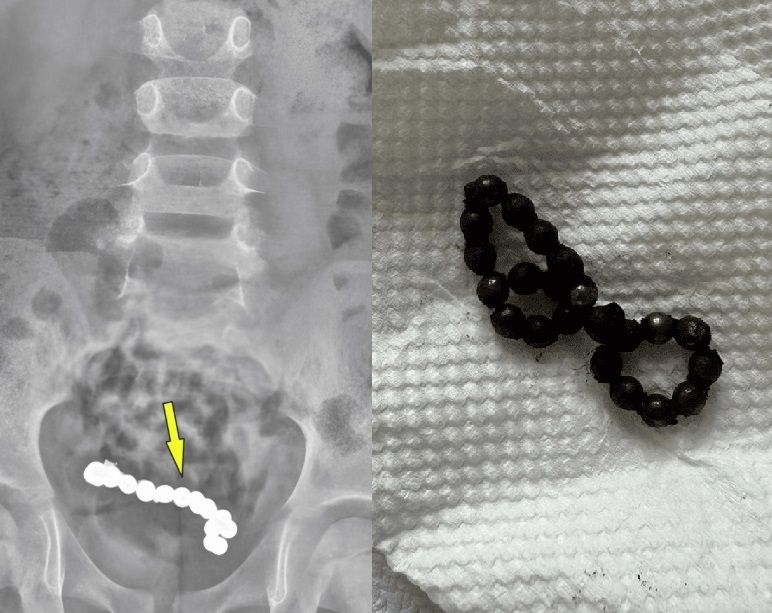

복통을 호소하던 남아의 뱃속에서 자석 뭉치가 발견된 사례가 보고됐다. 출처=큐레우스

초기에는 단순 변비로 판단돼 관련 치료를 받았지만, 증상이 호전되지 않았다. 이에 추가로 엑스레이 검사를 받은 결과, 하복부에 동글한 이물질이 여러 개 붙어 있는 것을 확인했다.

현지 소아과 병원 의료진은 복강경 수술을 진행했고, 소년의 뱃속에서 22개의 자석이 발견됐다.

이 자석들은 서로 붙어 팔찌처럼 보이는 상태였다.